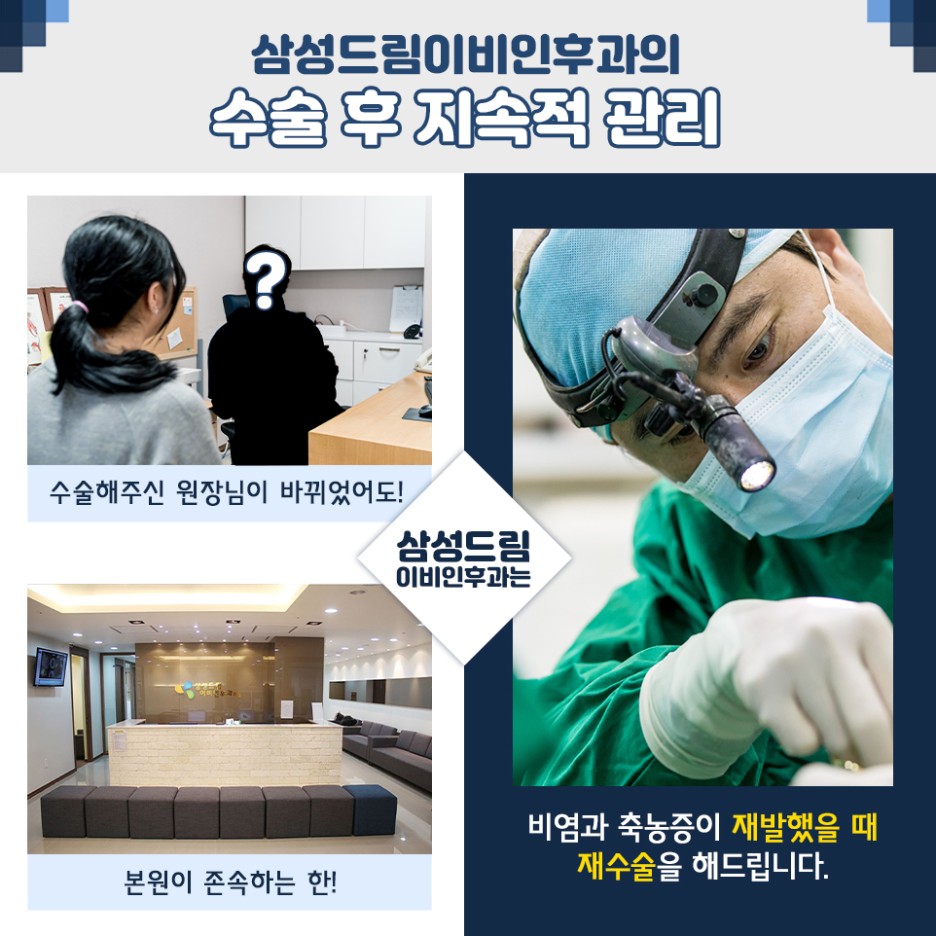

그래서 체계적인 과정은 물론 소통부터 진료, 사후관리까지 꼼꼼히 진행할 수 있도록 플랜을 만들고 있었습니다. 축농증 수술 후 체크할 때 돌봄이 어떻게 이뤄지는지 꼼꼼히 확인해야 할 부분인데 더 초점을 맞춰야 할 부분은 이와 관련된 관리가 꾸준히 유지되는지 확인해야 했습니다. 사후관리와 회복의 도움이 잘 진행되지 않으면 중추의 여러 부작용에 노출될 수 있기 때문입니다.

저희 병원에서는 비염과 축농증에 대한 세심한 관리 프로그램을 준비하고 있기 때문에 걱정도 줄일 수 있었습니다. 축농증 치료는 복잡한 코 내부 구조를 의료진이 확인하고 집도하는데 정교한 장비가 요구됐는데요. 축농증 상황에 맞게 가느다란 장비를 사용하여 보다 세밀하게 코 구조를 체크하여 진행하고 있기 때문에 보다 만족감 높은 결과를 만들 수 있었습니다. 더욱이 염증이 있는 부분만 선택적으로 치료해 짧은 시간에 얻은 결과를 기대할 수 있었습니다.

코는 오감 중 후각 기능을 하는 부위입니다. 특히 호흡까지 함께 진행되기 때문에 보다 건강한 상태를 유지하는 것이 중요했습니다. 축농증으로 불편한 요소를 가지고 있는 경우 앞으로 치료를 계획하여 문제점을 개선했으면 좋겠습니다. 특히 축농증 수술 사례는 다양하게 존재하기 때문에 꼼꼼히 내용을 체크하는 것이 올바른 결정이라고 할 수 있습니다.

관리후에도 꾸준한 관심을 가지고 계셨으면 좋겠습니다. 그렇지 않으면 또 다른 치료가 요구되는 상황이 발생할 수 있기 때문에 신중하게 계획을 세워야 했습니다.